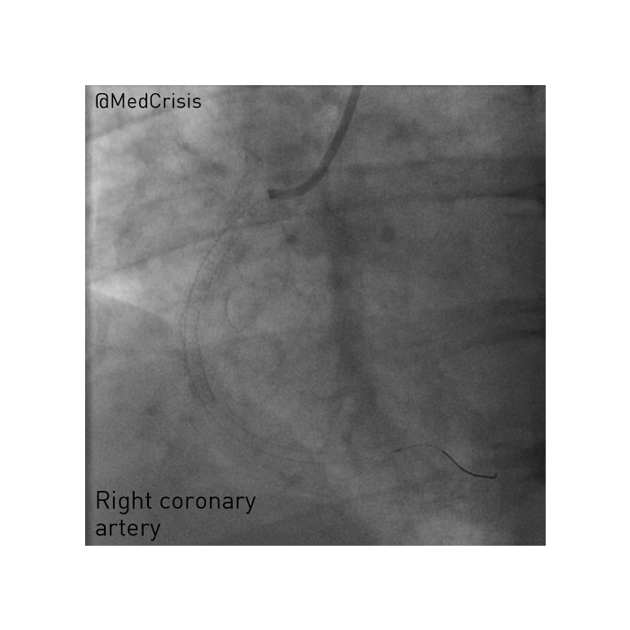

You can see even passing a 0.014” diameter wire restores some flow. The wire tip is in the posterior descending artery. Reperfusion is often when patients destabilise and indeed the patient’s heart rate dropped to 20bpm and blood pressure to 60mmHg but she responded quickly to atropine and fluid. In the proximal vessel, a filling defect can be seen which is a sizeable thrombus.

A 3.5mm wide and 38mm long drug-eluting stent was placed without complication in her RCA, producing a nice angiographic result. However, the long period of coronary occlusion may well have caused significant myocardial injury. She was kept under close observation.